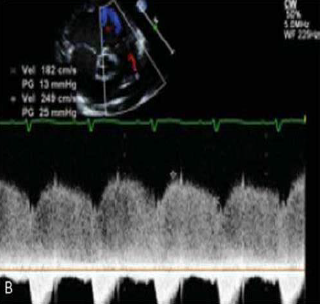

Ao realizar o ecocardiograma de um paciente de 8 meses de vida, evidencia-se apenas canal arterial pérvio conforme ilustrado na seguinte figura. Os sintais vitais do paciente são FC 110bpm PA 85x40 FR 48irpm. Qual é a estimativa da pressão da artéria pulmonar?